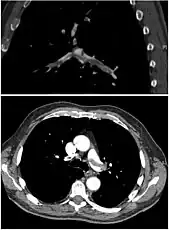

On CT scan, pulmonary emboli can be classified according to level along the arterial tree. -

Segmental and subsegmental pulmonary emboli on both sides -

CT pulmonary angiography showing a "saddle embolus" at the bifurcation of the main pulmonary artery and thrombus burden in the lobar arteries on both sides.

Assessing the accuracy of CT pulmonary angiography is hindered by the rapid changes in the number of rows of detectors available in multidetector CT (MDCT) machines.[53] According to a cohort study, single-slice spiral CT may help diagnose detection among people with suspected pulmonary embolism.[54] In this study, the sensitivity was 69% and specificity was 84%. In this study which had a prevalence of detection was 32%, the positive predictive value of 67.0% and negative predictive value of 85.2%. However, this study's results may be biased due to possible incorporation bias, since the CT scan was the final diagnostic tool in people with pulmonary embolism. The authors noted that a negative single slice CT scan is insufficient to rule out pulmonary embolism on its own. A separate study with a mixture of 4 slice and 16 slice scanners reported a sensitivity of 83% and a specificity of 96%, which means that it is a good test for ruling out a pulmonary embolism if it is not seen on imaging and that it is very good at confirming a pulmonary embolism is present if it is seen. This study noted that additional testing is necessary when the clinical probability is inconsistent with the imaging results.[55] CTPA is non-inferior to VQ scanning, and identifies more emboli (without necessarily improving the outcome) compared to VQ scanning.[56]